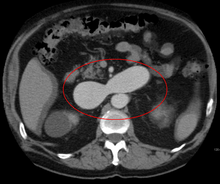

An arterial venous malformation of the left kidney and a simple cyst of the right kidney

An arterial venous malformation of the left kidney leading to aneurysmal dilatation of the left renal vein and inferior vena cava